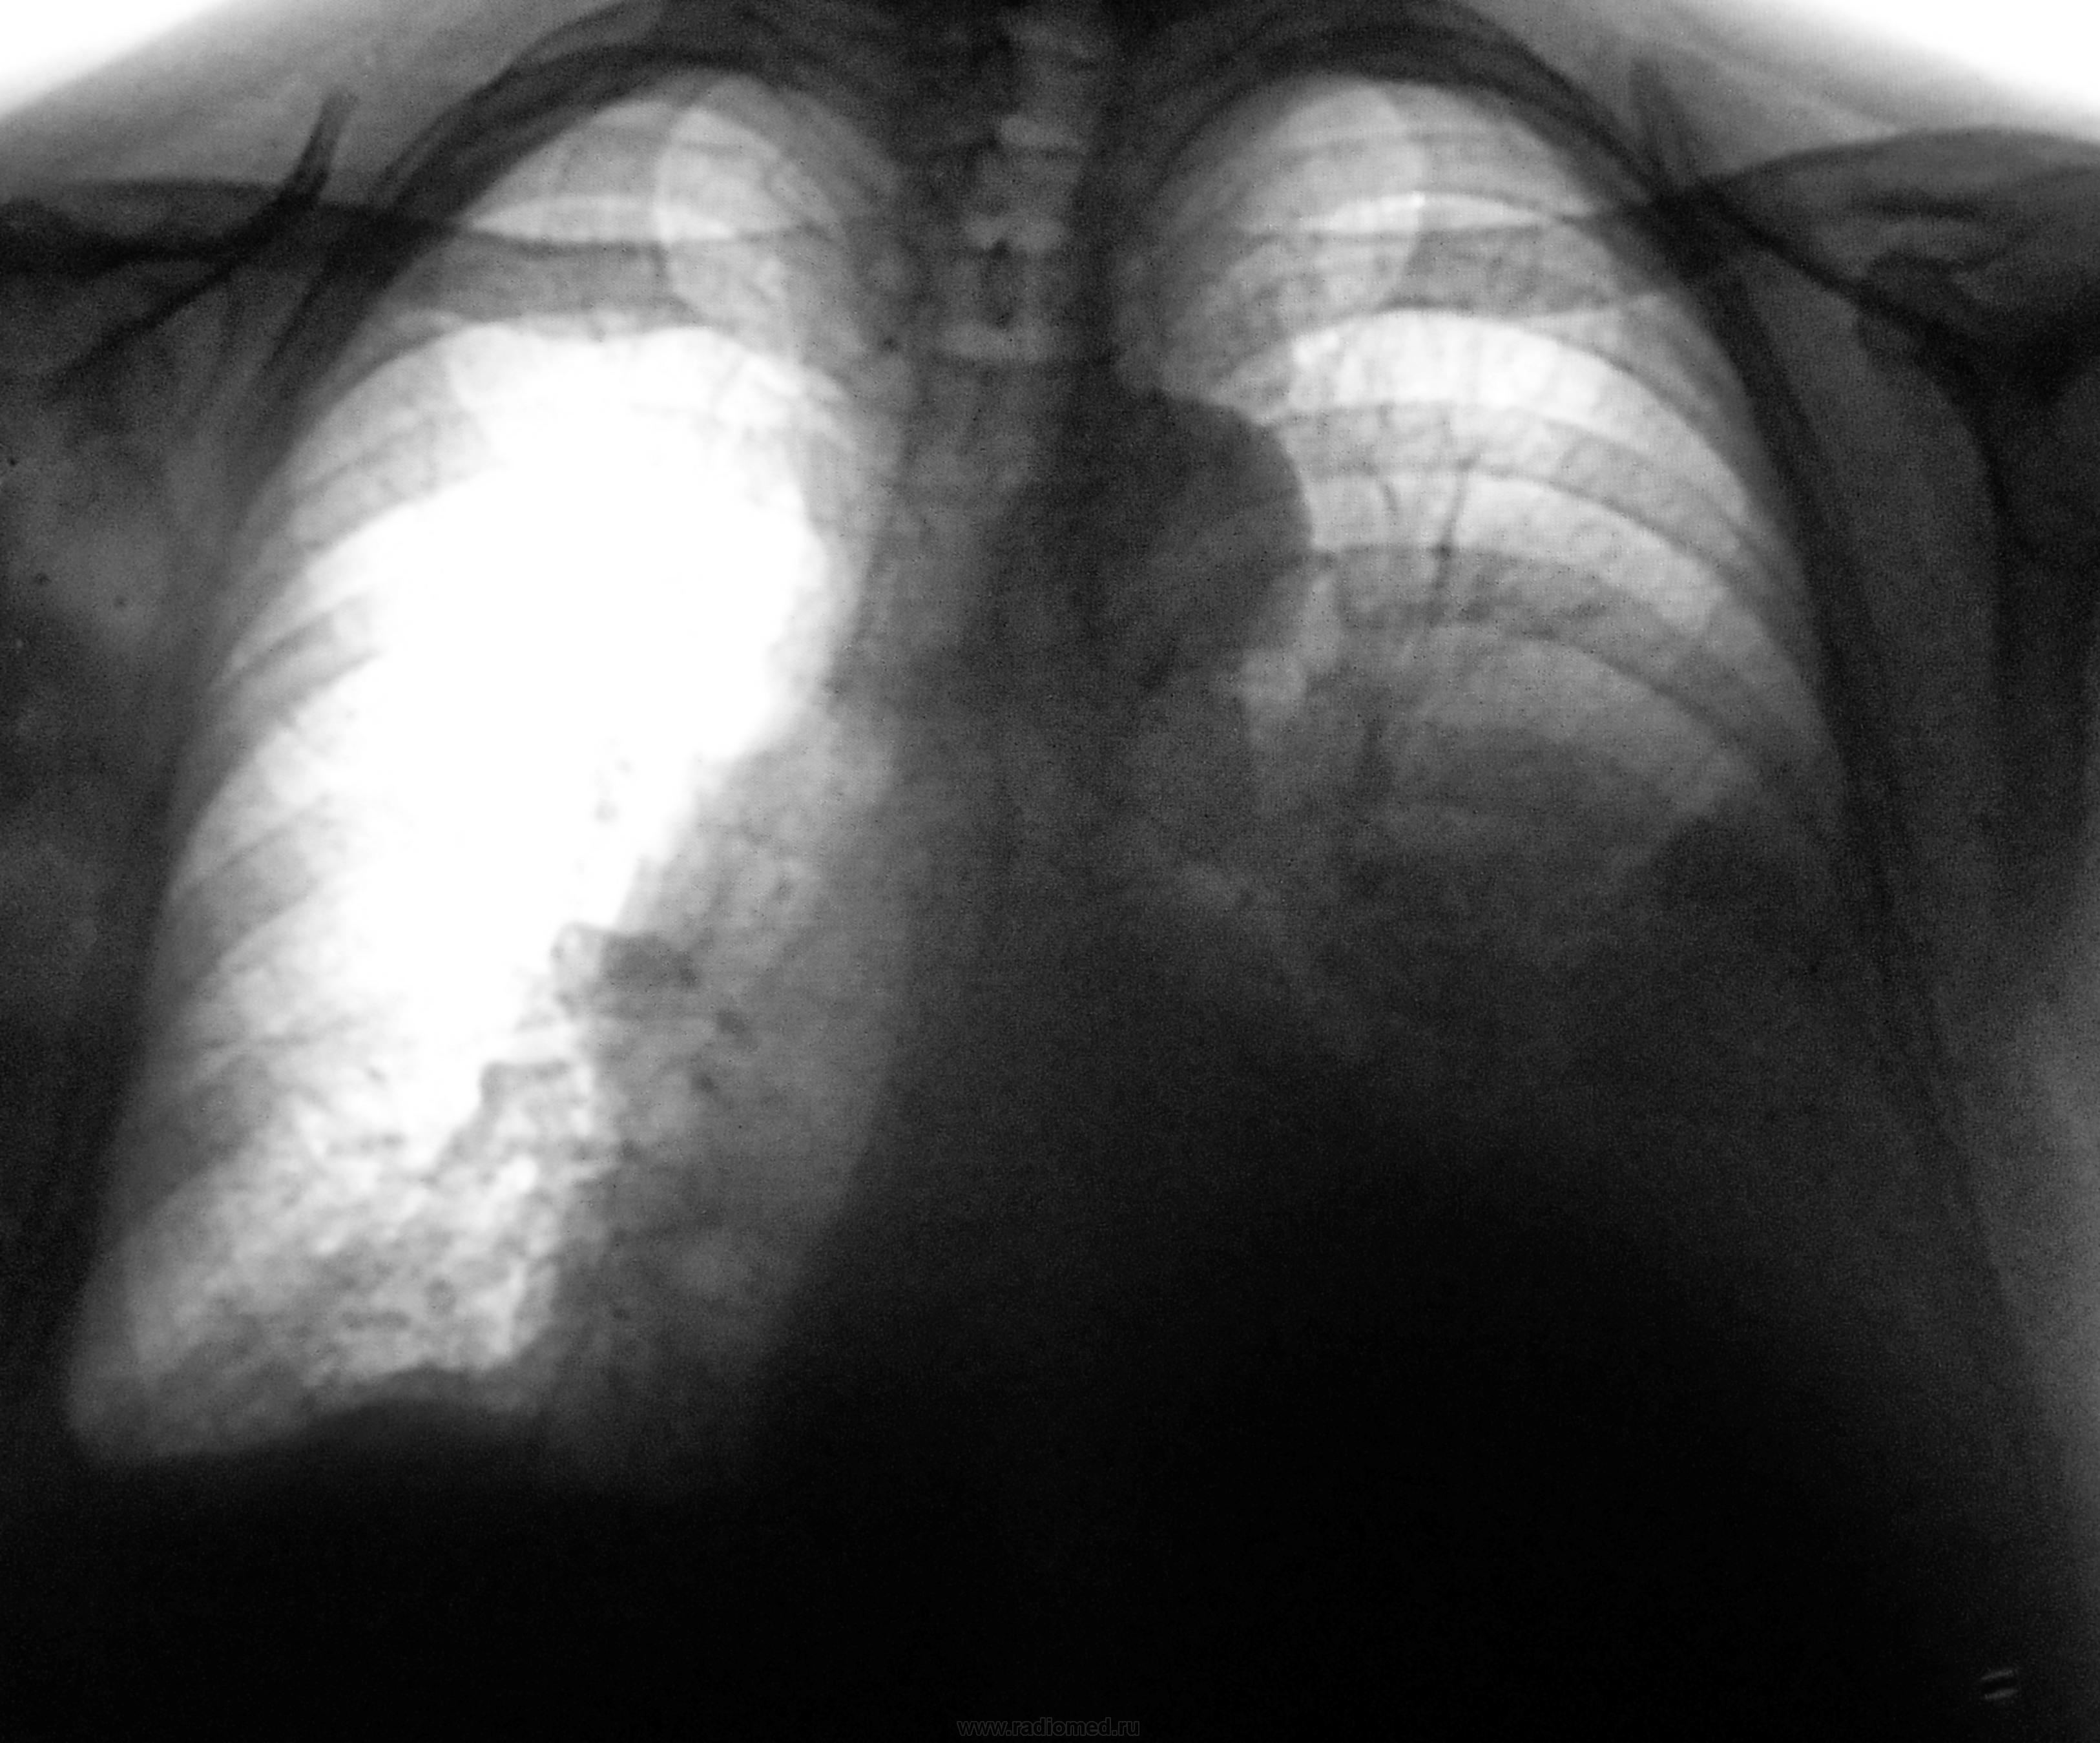

Интересно.Купол плоский,вероятно жидкость немного есть.Но что за фокусы в шестерке и проекции леваго корня?Подчеркнута межделевка-об онкологии надо задумоться влевом легком.

Согласен насчет округлой тени S6 слева. Думаю, что остальное плевральные дела: базально, по междолевке и в добавочных щелях. По передней стенке - осумкованный выпот. Не совсем понял справа - бифуркация смещена умеренно, отчего такое расширение срединной тени, за счет увеличения сердца? Первая мысль - опухоль с вторичным гидротораксом. Стесняюсь, но спрошу про результат пункции...

Тут, Валентин Львович, как в том анекдоте про солдата, который "всегда о бабе думает" (да простят меня дамы). А серьезно - все ж таки: гидроторакс с явным преобладанием слева, подозрительная тень в S6 слева, есть впечатление о её прилегании к плевральной щели. ФЛГ - профилактическая, то есть - жалоб особых нет, значит - копилось потихоньку. Ну, и как-то по принципу: от худшего к более приемлемым вариантам.

Двусторонний гидроторакс, слева - массивный, с элементами осумкования, кардидодилятация. Генез может быть воспалительным, онкологическим, кардиогенным, травматическим. Первые два наиболее вероятны. Эмпиема или узловая форма мезотелиомы. Достоверных онко-признаков не видно. Данных за мтс в ребра не вижу.

Согласен насчет округлой тени S6 слева. Думаю, что остальное плевральные дела: базально, по междолевке и в добавочных щелях. По передней стенке - осумкованный выпот. Не совсем понял справа - бифуркация смещена умеренно, отчего такое расширение срединной тени, за счет увеличения сердца? Первая мысль - опухоль с вторичным гидротораксом. Стесняюсь

, но спрошу про результат пункции...